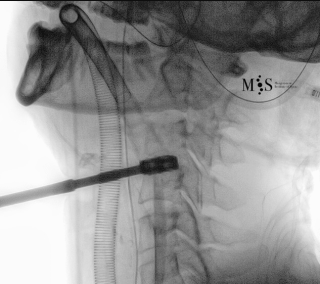

Imágenes de una cirugía de fusión cervical endoscópica

Animación de la inserción de una caja intersomática por vía endoscópica percutánea.

Nótese la apertura (expansión) de la pared posterior del disco al insertar la caja.